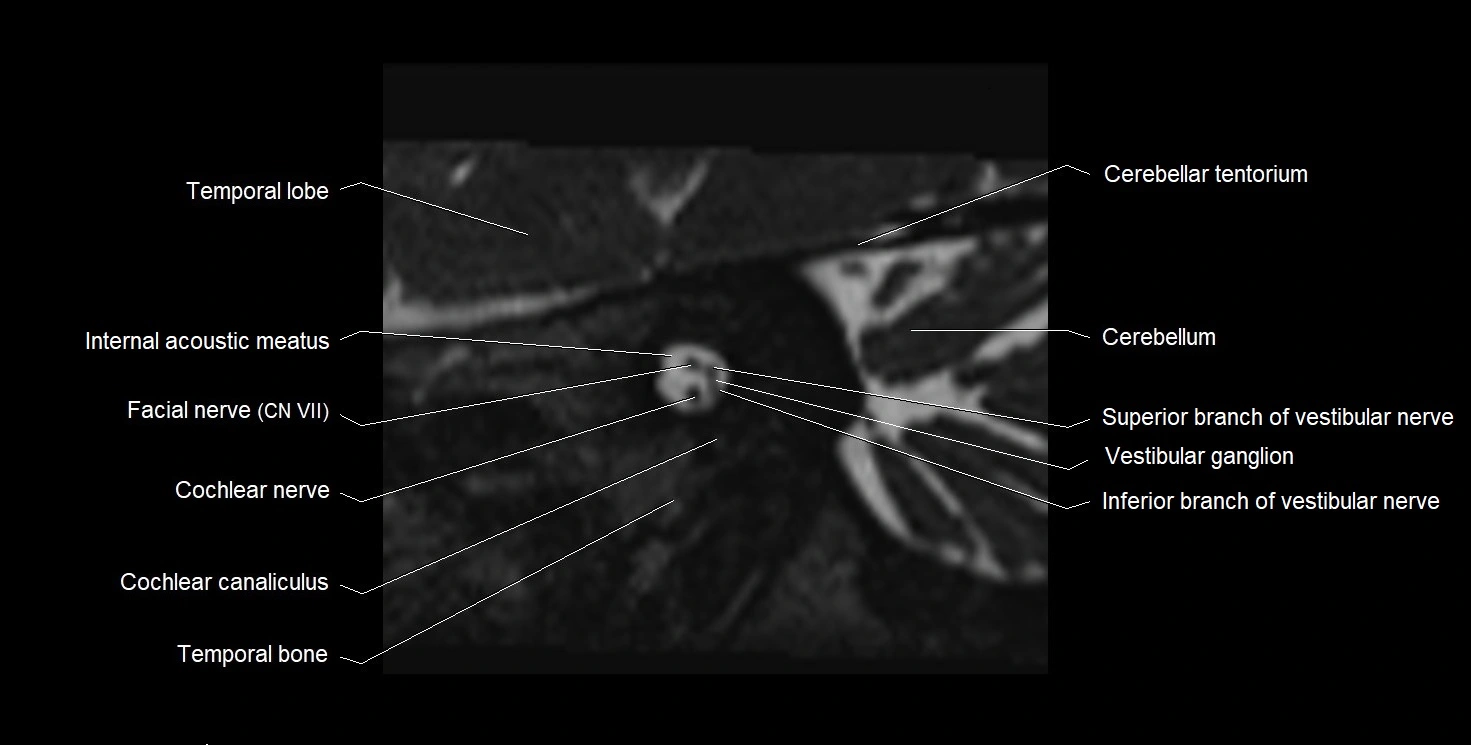

MRI images

image